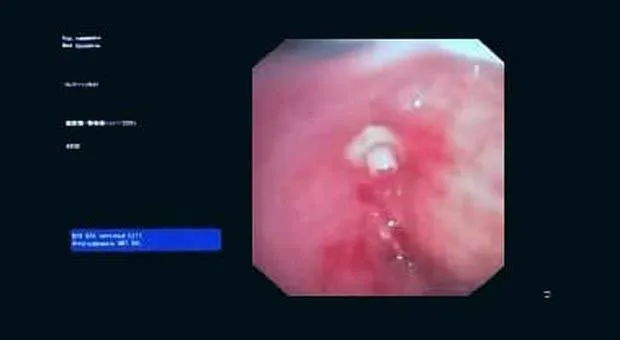

Вчера в отделении эндоскопии успешно апробировано окклюзия бронхоплеврального свища.

Пациент К. 1960 г.р., после правосторонней пульмонэктомии от 2019 г. поступил в отделение многоплановой хирургии. При плановой бронхоскопии выявлена несостоятельность культи правого главного бронха, устье свища до 0.3 см, откуда поступает слизисто-гнойное содержимое. В устье свища определяется сшивающая скоба. Также у пациента имеется дренажная трубка справа в 7 межреберье, подключаемая к активному отсосу.

Во время повторной бронхоскопии под интубационным наркозом установлен окклюдер из ИМН другого назначения (PULL THRU) в устье свища. Поперечные резиновые лепестки на окклюдере и скоба в устье свища должны надёжно фиксировать положение окклюдера.

Оборудование: видеобронхоскоп Olympus 180, окклюдер PULL THRU( Medivators)